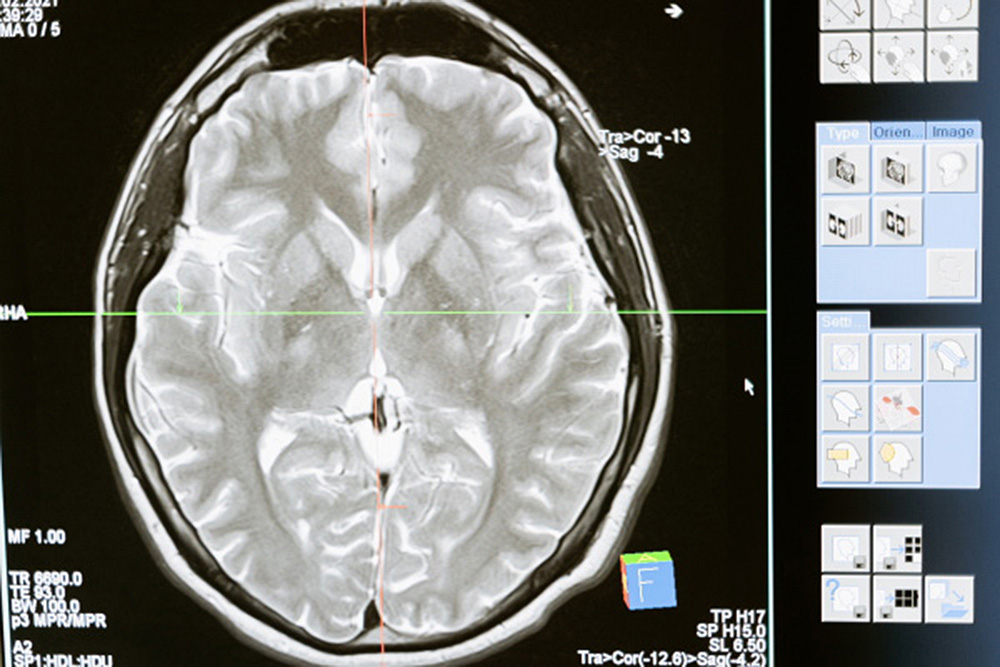

El proyecto, que lleva cinco años y poco más de 2 millones de dólares subsidiado por la Fundación Nacional de Ciencias (NSF), está en la búsqueda de ofrecer nuevos métodos prometedores para enfocar las ondas de ultrasonido a través del cráneo. Este proyecto podría conducir a un uso más amplio de las imágenes por ultrasonido, consideradas más seguras y menos costosas que la tecnología de resonancia magnética (RM).

Los resultados de los estudios realizados con representaciones de ultrasonido encontraron una nueva forma de enfocar la ecografía a través del cráneo y en el cerebro. Los cálculos fueron 100 veces más rápidos en comparación a las resonancias magnéticas que son voluminosas y extremadamente costosas.